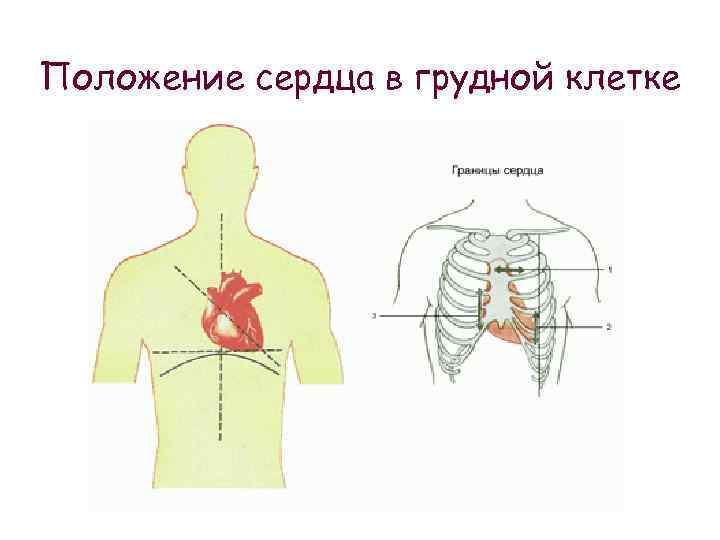

Расположение сердца у человека.

Анатомическое расположение сердца.

Сердце в грудной клетке расположено.

Где расположено сердце у человека анатомия.